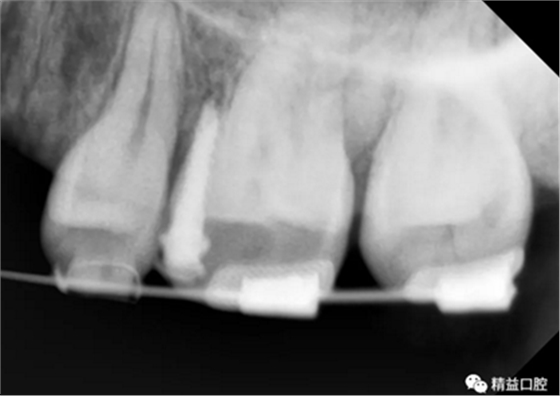

初次看到俊的牙片,我也驚訝到了,畢竟才27歲,上下門(mén)牙牙根吸收得非常嚴(yán)重,如果矯正,其中的風(fēng)險(xiǎn)還是非常大的。

矯正前全口曲斷片

從片子上可以清除看到,上牙門(mén)牙牙根吸收非常厲害。